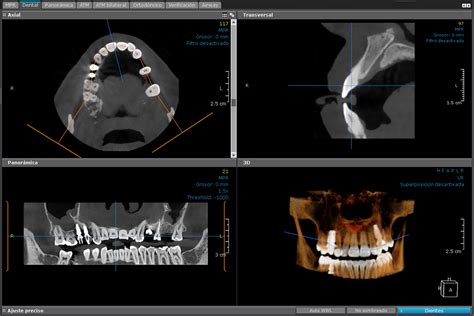

En la imagen de la portada (corte de un TAC en 3D) se observa un quiste naso-palatino, uno de los más comunes de la cavidad oral.

Quiste naso-palatino en TAC 3D